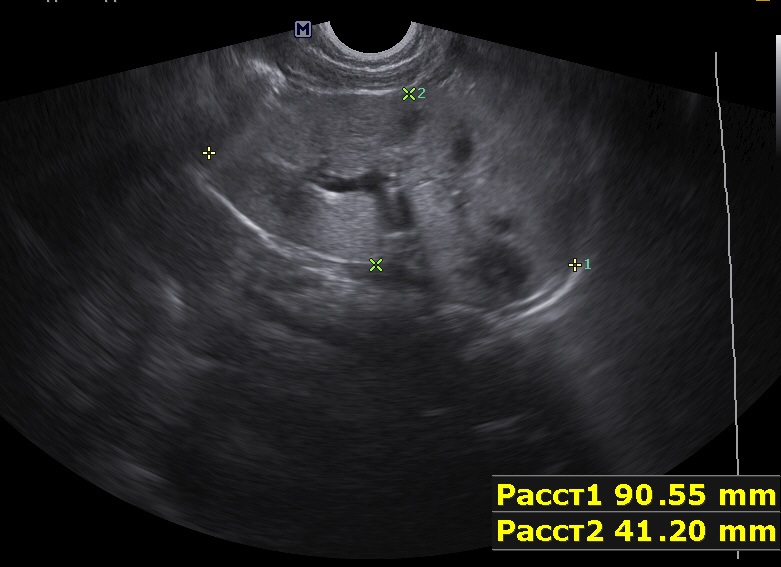

Ребенок 9мес, старшая сестра 9лет с ювенильным поликистозом (в н.в. ХБП 2).

Первые изменения в 1 мес, увеличение размеров почек.

Осмотрен мной ребенок впервые, обращено внимание на большие почки, 90х40мм, паренхима 17-18мм, корковый слой гиперэхогенный, пирамидки дифференцируются. Линейным датчиком определяется: кисты или расширенные канальцы в пирамидках. Структура печени в 1 мес была не изменена, в н.в. отмечается перипортальный фиброз, размеры печени и селезенки увеличены.

Поставил медуллярную кистозную дисплазию, почитав литературу предполагаю нефронофтиз Фанкони, но к сожалению не нашел картинки только описание данной болезни. Поделитесь своим мнением.

левая почка.jpg